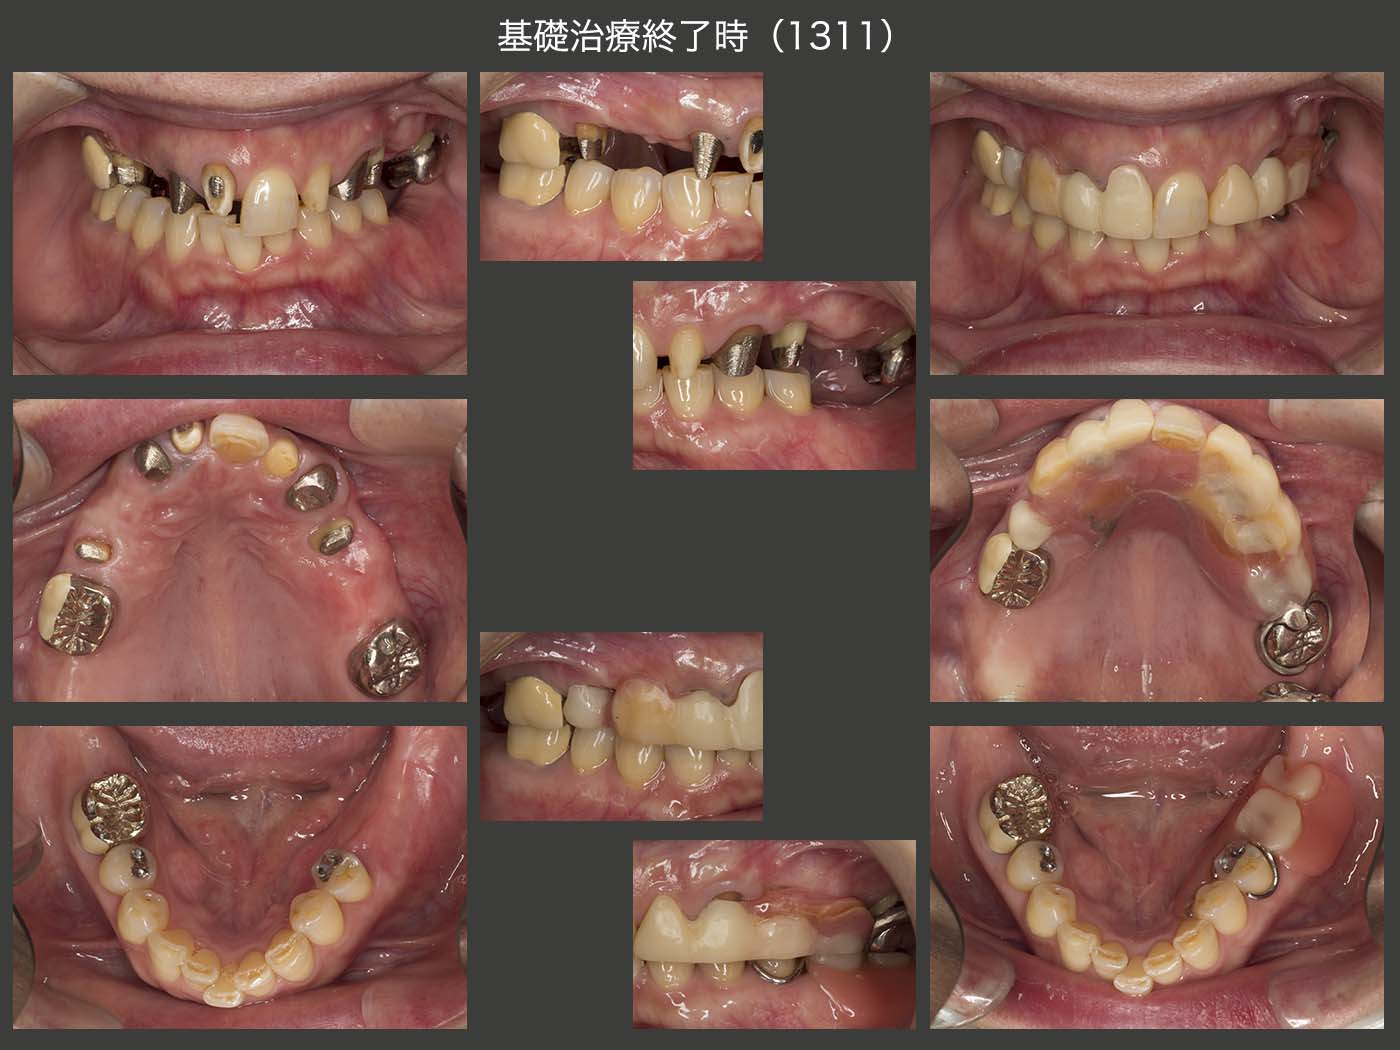

初診時の右側方面観の写真は,下顎偏心位で撮影された可能性が高いが,2012年7月の中心咬合位での右側方面観では,義歯のスペースが全くない状態であった.右上3は歯根破折しており,抜去した.そこでまず,上顎義歯の維持安定を図るために,右上1,2および左上2,3を支台歯に組み込んだ.動揺の大きかった右上4および抜髄した左上4は残根状にして,力から開放した.なお,右上4は歯周ポケットが最大6mm,左上4は8mm認められた.下顎位を確保するために,暫くの間健全歯である左上1を支台歯として取り込まないようにした.

2012年11月,ここでさらに上顎義歯の安定を図るために,非機能歯であり,上顎顎堤にとっては加圧要素となる右下7を右上6部に移植することにした.ドナー歯に挻出力を与え,抜歯しやすいように工夫した.受容側においては,歯槽骨中央部にメスで切開を加え,頰側の歯槽骨を側方に押し広げた.また,13年1月に左上4(スライドにはないが),および2月に右上5の歯周外科を行った.つぎに7月,歯根破折によるフィステルがみられた右上1を再植した.破折位置は浅く,本来は矯正的挻出の範疇であるが,固定源の問題,治療期間の観点から再植を選んだ.